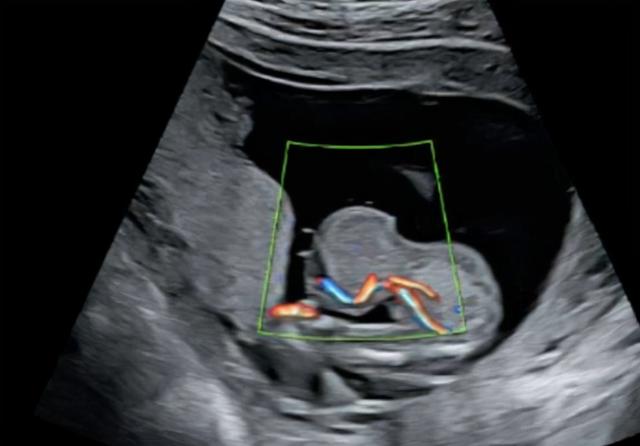

但是,也不是没有例外,因为在宫外孕中,有一种“宫外孕”叫做“腹孕”。在这种情况下,孕妇有1%的机会生出胎儿。

什么是腹腔?

妊娠呢?简而言之,就是胎儿长在了腹腔之中,在孕妇中,腹腔妊娠的出现概率,大约是三万分之一,和肝脏妊娠一样,都是极其罕见的。

虽然腹腔妊娠非常危险,但是,却也有成功案例,比方说在2007年12月,一名在腹腔中足月发育的胎儿,成功诞生于西安市的西京医院中,这也是我国首例腹腔妊娠成功诞生的婴儿,被取名为“小奇迹”。

不过,虽然母子平安,但是过程却是非常心惊动魄的,因为仅是在怀孕生产过程中,产妇就经历了多次转院,最终由宝鸡市转到了西安市,经过数小时的手术,才终于将孩子平安生了下来。

还有在2019年的时候,江西的一名产妇,也是“腹腔妊娠”后成功生产,不过,和上文中陕西的那名孕妇不同的是,江西的这名孕妇,完全是“福大命大”。

为何这么说呢?因为这名孕妇在怀孕初期进行了简单的检查之后,就再也没有去往医院进行过产检,一直到孩子足月了,才终于去往医院待产,结果在检查的时候,才知道胎儿竟然不在子宫里,而是长在了腹腔里。

幸运的是,这个足月的“腹腔胎儿”也成功诞生了,创造了又一个奇迹。所以,如果大家怀孕了,那么,一定要定期去医院进行产检,确保孩子可以平安健康发育。